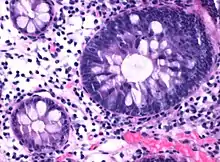

Micrograph of hyperplastic polyp

Histopathologically, there are two main types of hyperplastic polyps, which have genetic differences, as well as different histologic structure, but no significant differences clinically.[4] The two main types of hyperplastic polyps are microvesicular mucin-rich type and goblet cell-rich type.[1] A mucin-poor type with eosinophilic cytoplasm, which is rare, was previously described.[4] However, the mucin poor type is no longer considered a distinct subtype.[1]

The luminal portion has a serrated ("saw tooth") appearance formed by tufts or folds of abundant apical cytoplasm. It contains glands with star-shaped lumina.[4] There are crypts that are elongated but straight, narrow and hyperchromatic at the base. All crypts reach to the muscularis mucosae.[4] The basement membrane is frequently thickened.[4]

Elongated, fat crypts and little to no serration. Therefore, they may not be obvious without comparing to adjacent normal intestinal wall.[4]

They are filled with goblet cells, extending to surface, which commonly has a tufted appearance.[4]